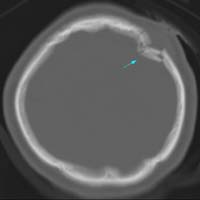

<µÎ°³°ñÀý>

<¼±»ó°ñÀý>

<ÇÔ¸ô°ñÀý>

µÎ°³°ñÀýÀÇ

³úCT ¼Ò°ß

<±Þ¼º°æ¸·¿ÜÃâÇ÷>

<¸¸¼º°æ¸·ÇÏÃâÇ÷>

ÁÂ)

ÁÂÃø ÃøµÎºÎ¿¡ ·»Áî¸ð¾çÀÇ °æ¸·¿Ü ÃâÇ÷ÀÇ

CT¼Ò°ß

¿ì) °æµµÀÇ ¿Ü»ó¿¡µµ

¹ß»ýÇÏ°Ô µÇ´Â ¸¸¼º°æ¸·ÇÏÃâÇ÷ÀÇ ³úMRI¼Ò°ß